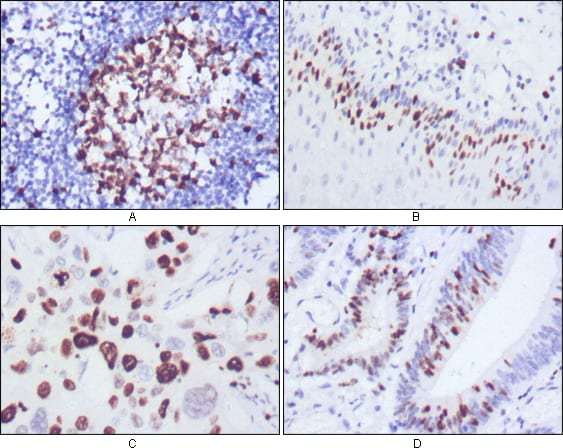

分类: 科研抗体货号: 20354别名: KIA; Ki-67; MKI67应用: IHC,IF反应种属: Human,Mouse,Rat,Rabbit,Monkey